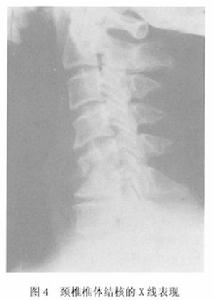

圖4根據病史臨床表現、體徵X線片、CTMRI及實驗室檢查,臨床確定診斷不難。

(1)骨關節改變:X線片上以骨質破壞和椎間隙狹窄表現為主一般在發病後2個月內沒有陽性X線徵象。因此,對可疑病例需重複攝片或採用其他檢查中心型的骨質破壞集中在椎體中央,在側位片比較清楚。很快出現椎體壓縮成楔形,前窄後寬。也可以侵犯至椎間盤累及鄰近椎體。邊緣型的骨質破壞集中在椎體的上緣或下緣很快侵犯至椎間盤,表現為椎體終板的破壞和進行性椎間隙狹窄,並累及鄰近兩個椎體(圖4)。邊緣型的骨質破壞與楔形壓縮不及中心型明顯,故脊柱後凸不重。